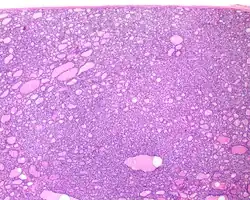

Histopathology of NIFTP, H&E stain.[1]

1. ^ Image by Mikael Häggström, MD. Reference for findings: Rachel Jug, M.B.B.Ch., B.A.O., David Poller, M.D., Xiaoyin "Sara" Jiang, M.D. "NIFTP". Pathology Outlines.{{cite web}}: CS1 maint: multiple names: authors list (link) Last author update: 10 May 2018